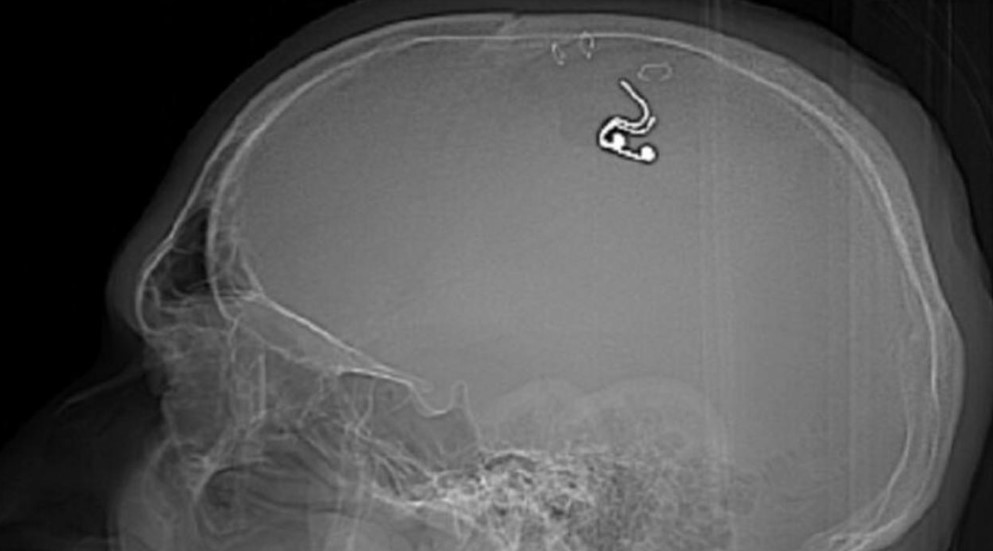

TRT Haber’in Newsweek’ten aktardığı habere göre; Michael Raduga isimli Rus uyruklu adam, kafasına ev tipi bir matkap kullanarak rüyalarını kontrol etmesine izin verecek bir çip yerleştirdi.

Telegram gönderisinde, "Bir matkap aldım, kafamda bir delik açtım ve beynime bir elektrot yerleştirdim" dedi.

Raduga ayrıca görüntüleri Twitter sayfasında paylaştı ve ameliyatı sırasında kan kaybından neredeyse ölüyor olmasına rağmen, sonuçların "gelecekteki rüya kontrol teknolojileri için harika umutlar" açtığını söyledi.